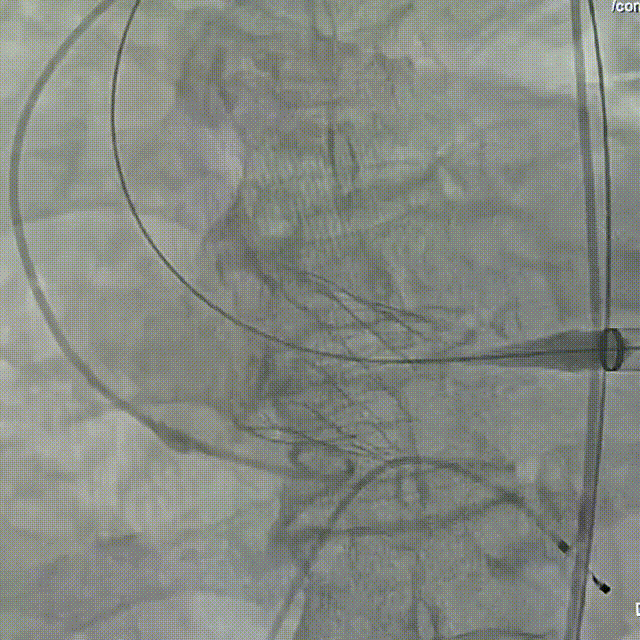

辅入路猪尾根部造影(右窦居中)

瓣膜初始定位

瓣膜开花后造影确认位置

起搏下释放瓣膜至全展开

全展开后造影评估

瓣膜打平造影评估

瓣膜位置可,形态可

脱钩后造影,瓣膜无位移,形态可

弓部剪影,无瓣周漏,升主无损伤